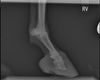

alte Hufbeinrotation nach Hufrehe mit Zubildungen an der Hufbeinspitze, Aufnahme von Dr. Menzel, Tierarztpraxis Thurmading